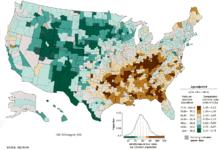

United States

The leading cause of death in the United States was tobacco. However, poor diet and lack of exercise may soon surpass tobacco as a leading cause of death. These behaviors are modifiable and public health and prevention efforts could make a difference to reduce these deaths.[4]

Mortality from modifiable risk factors

Chronic diseases such as heart disease, stroke, diabetes, obesity and cancer have become the most common and costly health problems in the United States. In 2014, it was projected that by 2023 that the number of chronic disease cases would increase by 42%, resulting in $4.2 trillion in treatment and lost economic output.[119] They are also among the top ten leading causes of mortality.[120] Chronic diseases are driven by risk factors that are largely preventable. Sub-analysis performed on all deaths in the United States in the year 2000 revealed that almost half were attributed to preventable behaviors including tobacco, poor diet, physical inactivity and alcohol consumption.[121] More recent analysis reveals that heart disease and cancer alone accounted for nearly 46% of all deaths.[122] Modifiable risk factors are also responsible for a large morbidity burden, resulting in poor quality of life in the present and loss of future life earning years. It is further estimated that by 2023, focused efforts on the prevention and treatment of chronic disease may result in 40 million fewer chronic disease cases, potentially reducing treatment costs by $220 billion.[119]

Minority populations

Health disparities are increasing in the United States for chronic diseases such as obesity, diabetes, cancer, and cardiovascular disease. Populations at heightened risk for health inequities are the growing proportion of racial and ethnic minorities, including African Americans, American Indians, Hispanics/Latinos, Asian Americans, Alaska Natives and Pacific Islanders.[130]

According to the Racial and Ethnic Approaches to Community Health (REACH), a national CDC program, non-Hispanic blacks currently have the highest rates of obesity (48%), and risk of newly diagnosed diabetes is 77% higher among non-Hispanic blacks, 66% higher among Hispanics/Latinos and 18% higher among Asian Americans compared to non-Hispanic whites. Current U.S. population projections predict that more than half of Americans will belong to a minority group by 2044.[131] Without targeted preventive interventions, medical costs from chronic disease inequities will become unsustainable. Broadening health policies designed to improve delivery of preventive services for minority populations may help reduce substantial medical costs caused by inequities in health care, resulting in a return on investment.